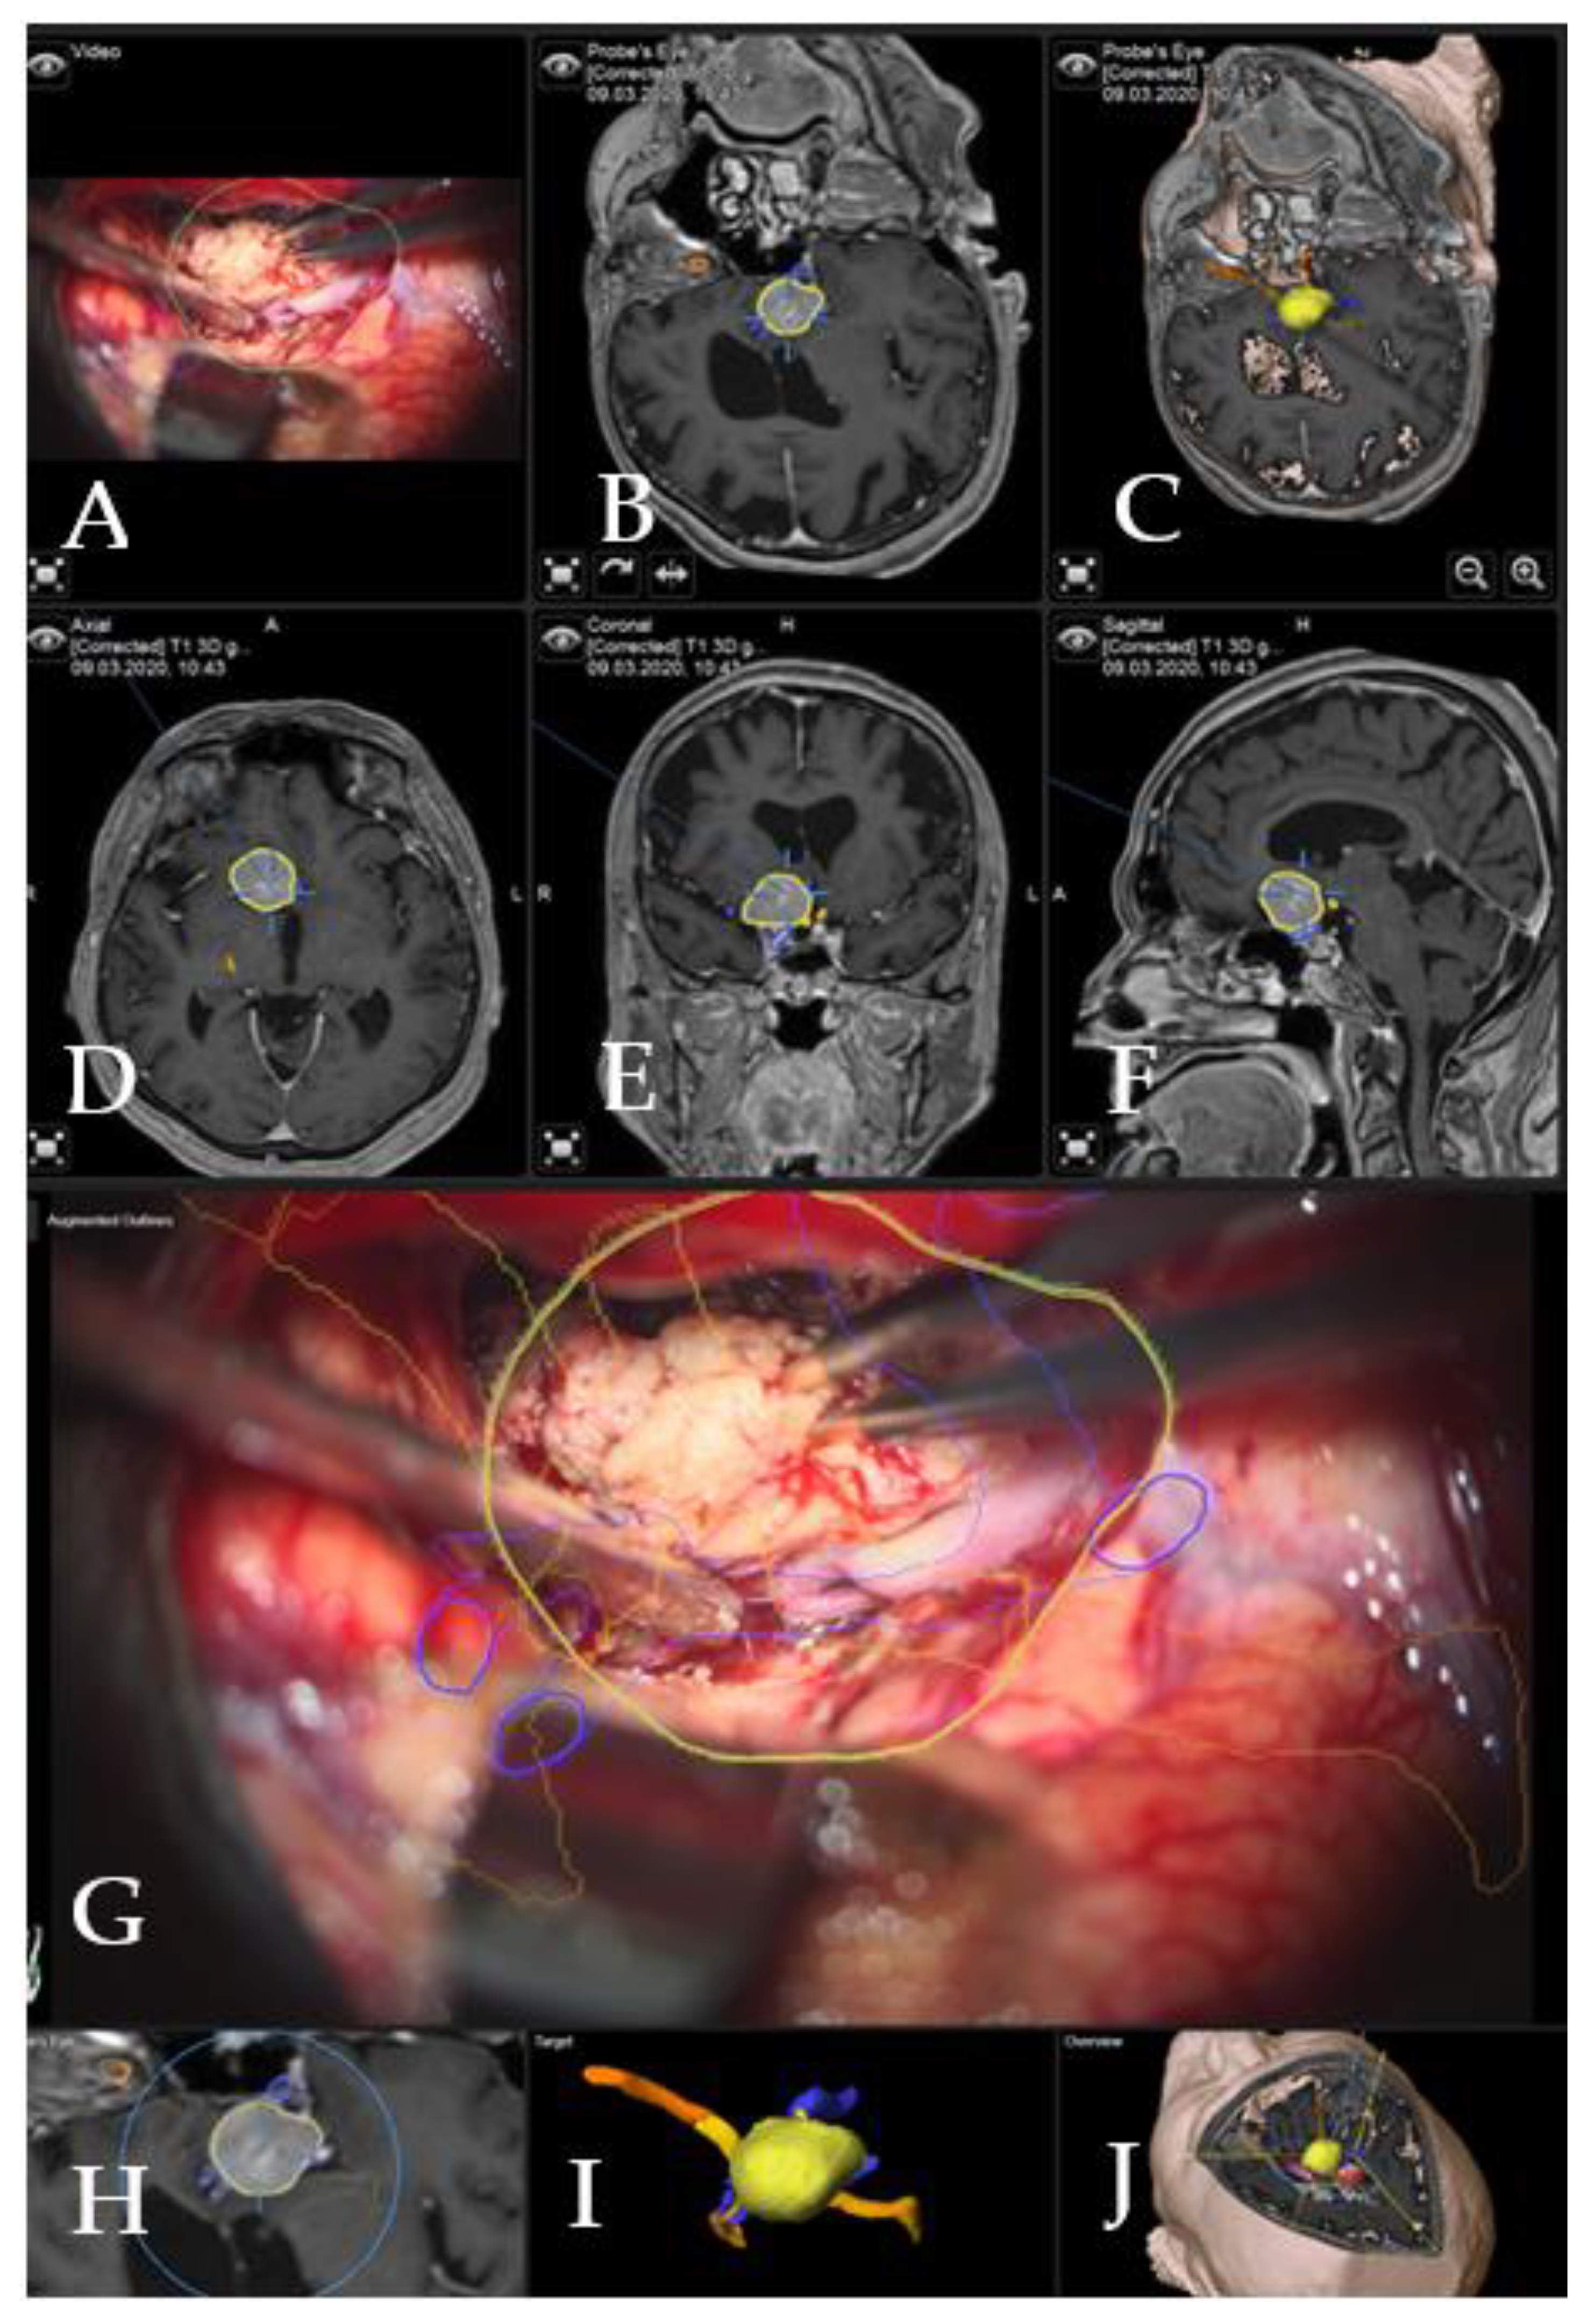

Illustrative Cases